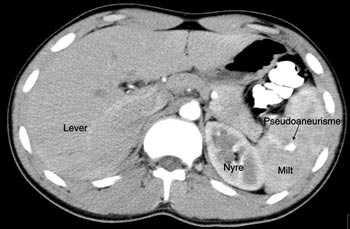

Pasient 1. En 16 år gammel gutt ble henvist til lokalsykehuset med spørsmål om miltskade. Han hadde seks dager tidligere falt under fotballtrening. Pasienten kom gående og klagde over magesmerter. CT-undersøkelse supplert med arteriell kontrastfase gav tydelig fremstilling av en rund, velavgrenset og høyattenuerende lesjon (fig 2a). På bildene fra vanlig venøs kontrastfase var denne strukturen dårligere fremstilt (fig 2b). Pseudoaneurisme ble mistenkt. Skaden ble vurdert som grad IV. Pasienten ble overflyttet til Ullevål universitetssykehus hvor det ble utført angiografi som bekreftet diagnosen. Deretter foretok man embolisering (fig 3). Prosedyren var vellykket og pasienten ble utskrevet etter én uke.

I litteraturen er det beskrevet redusert sensitivitet og spesifisitet for pseudoaneurismer ved CT-undersøkelse sammenholdt med angiografi (8), men undersøkelsene er som oftest kun gjort i venøs kontrastfase. I flere studier er det benyttet forsinkelse fra kontrastinjeksjon til bildeopptak på mellom 70 og 85 sekunder som tilsvarer sen eller venøs kontrastfase (1, 9, 10). CT-bildene fra undersøkelsen av pasient 1 illustrerer at dette kan vanskeliggjøre diagnostikken. I tillegg er det viktig å vite at vaskulære lesjoner kan presentere seg forsinket. Det viser bildene av pasient 2. CT-undersøkelse i arteriell og venøs fase etter 5 – 7 dager i tillegg til undersøkelse ved innkomst er derfor anbefalt (2, 6).